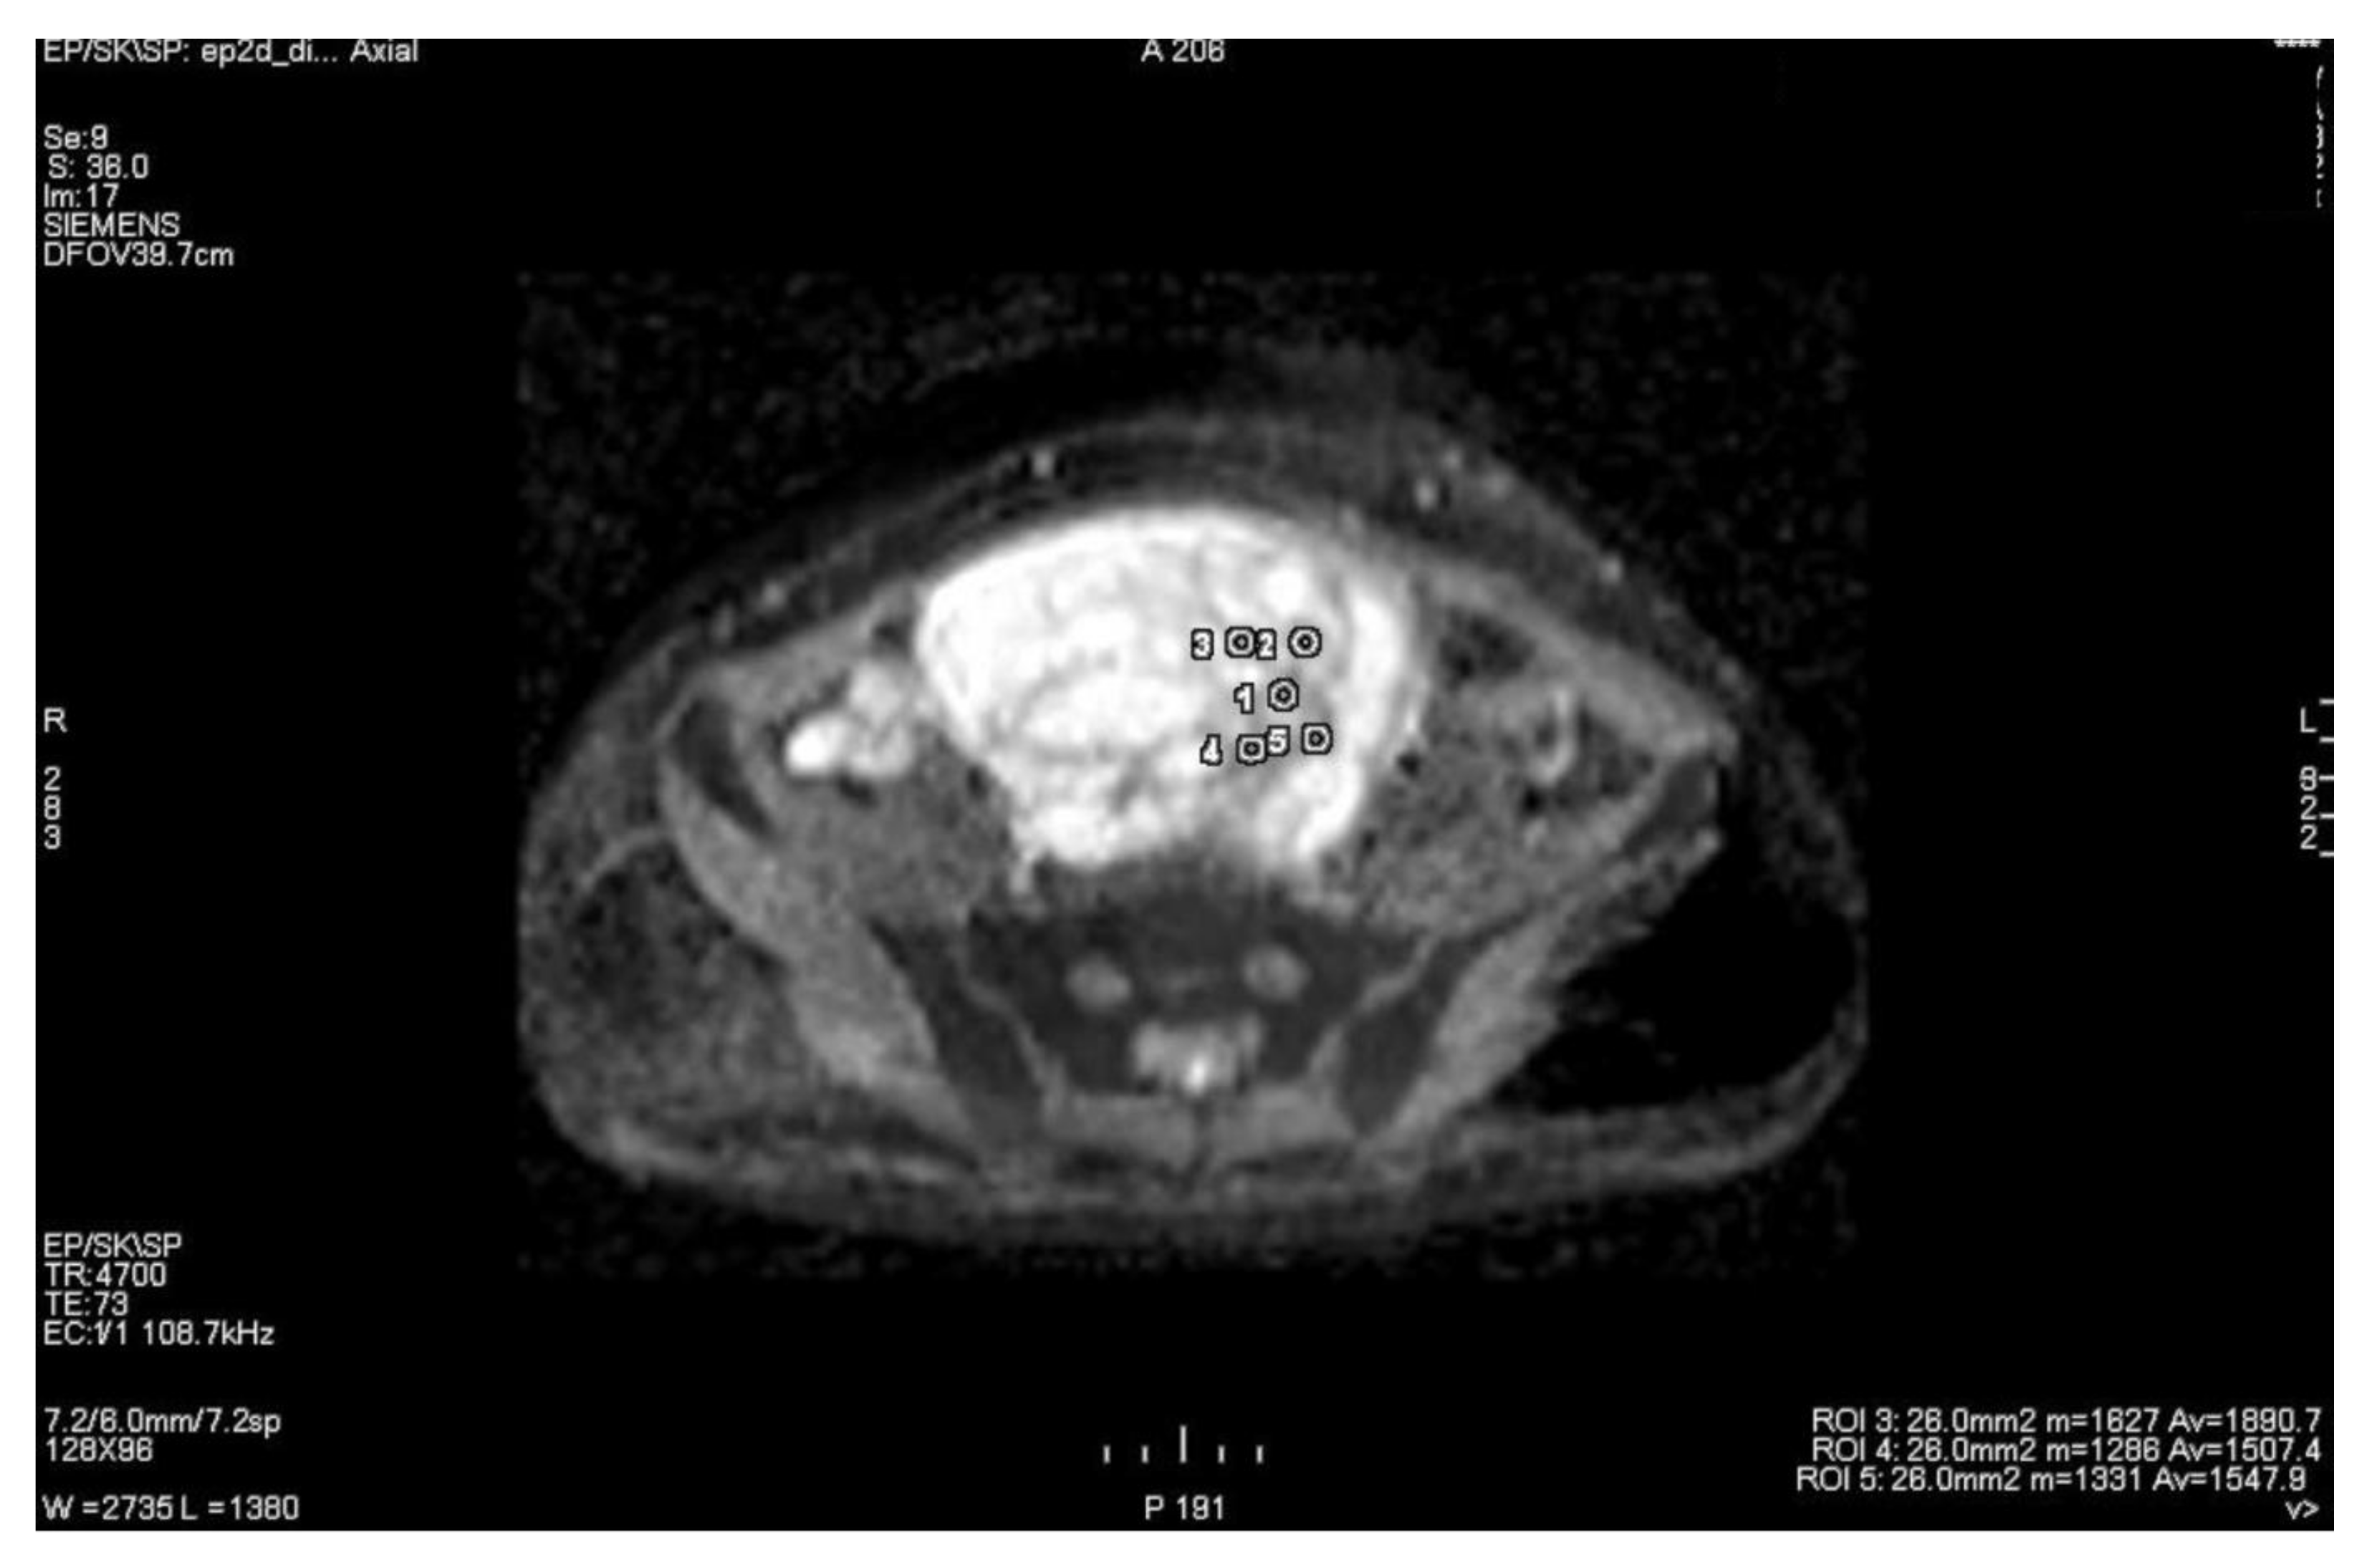

3.1. Primary Tumor DWI